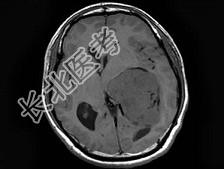

- 单项选择题男,27岁, 一过性黑矇发作半年伴记忆力下降,听觉性失语, 双眼同向性右侧视野缺损,无头痛、呕吐, MRI平扫及增强扫描,最可能的诊断为 ( )

A、侧脑室脑膜瘤

B、侧脑室室管膜瘤

C、侧脑室乳头状瘤

D、侧脑室星形细胞瘤